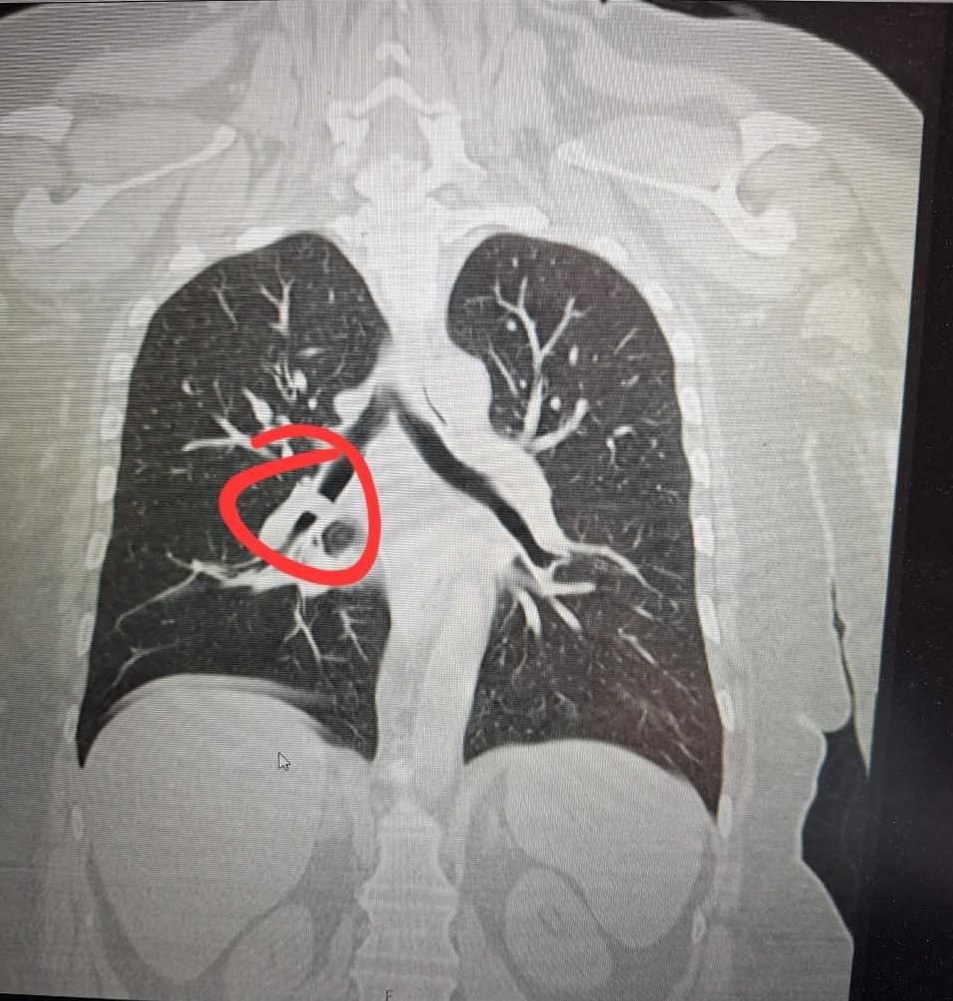

Uvođenjem bronhoskopskih procedura omogućeno je pravovremeno otkrivanje malignih i drugih ozbiljnih bolesti pluća, uključujući karcinom pluća, čime se značajno poboljšavaju mogućnosti liječenja i prognoza bolesti.

Od početka rada do danas realizirano je oko 300 bronhoskopija, što potvrđuje značaj i opravdanost uvođenja ovih usluga. Posebno je važno istaći da je uz pomoć nove opreme uspješno izvršena ekstrakcija stranog tijela iz disajnih puteva. Ova intervencija predstavlja važan medicinski iskorak, jer zahtijeva visoku stručnost, adekvatnu opremu i timski rad. Pravovremenim uklanjanjem stranog tijela spriječene su potencijalno ozbiljne komplikacije, poput gušenja, infekcija ili oštećenja plućnog tkiva, čime je direktno spašen i poboljšan kvalitet života pacijenta.